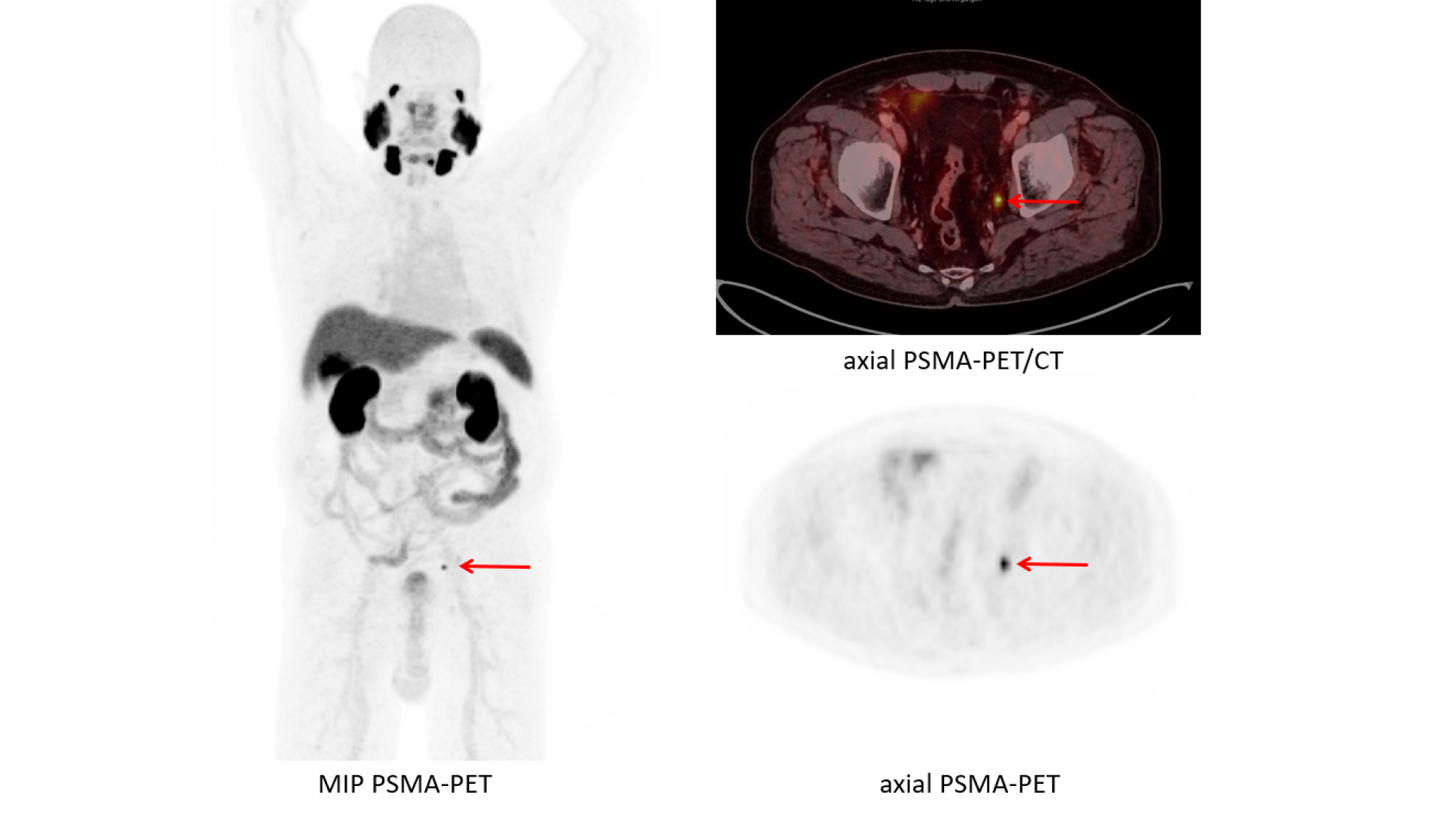

What To Do With a Positive PSMA PET and Negative Conventional Imaging in Patients With Prostate Cancer

Is PSMA PET/CT More Beneficial than Bone Scintigraphy in Detecting

Guiding management of therapy in prostate cancer: time to switch

PSMA-PET is rapidly changing the standard of care for prostate

Guiding management of therapy in prostate cancer: time to switch

Sequencing of Conventional and PSMA-PET Imaging in Prostate Cancer